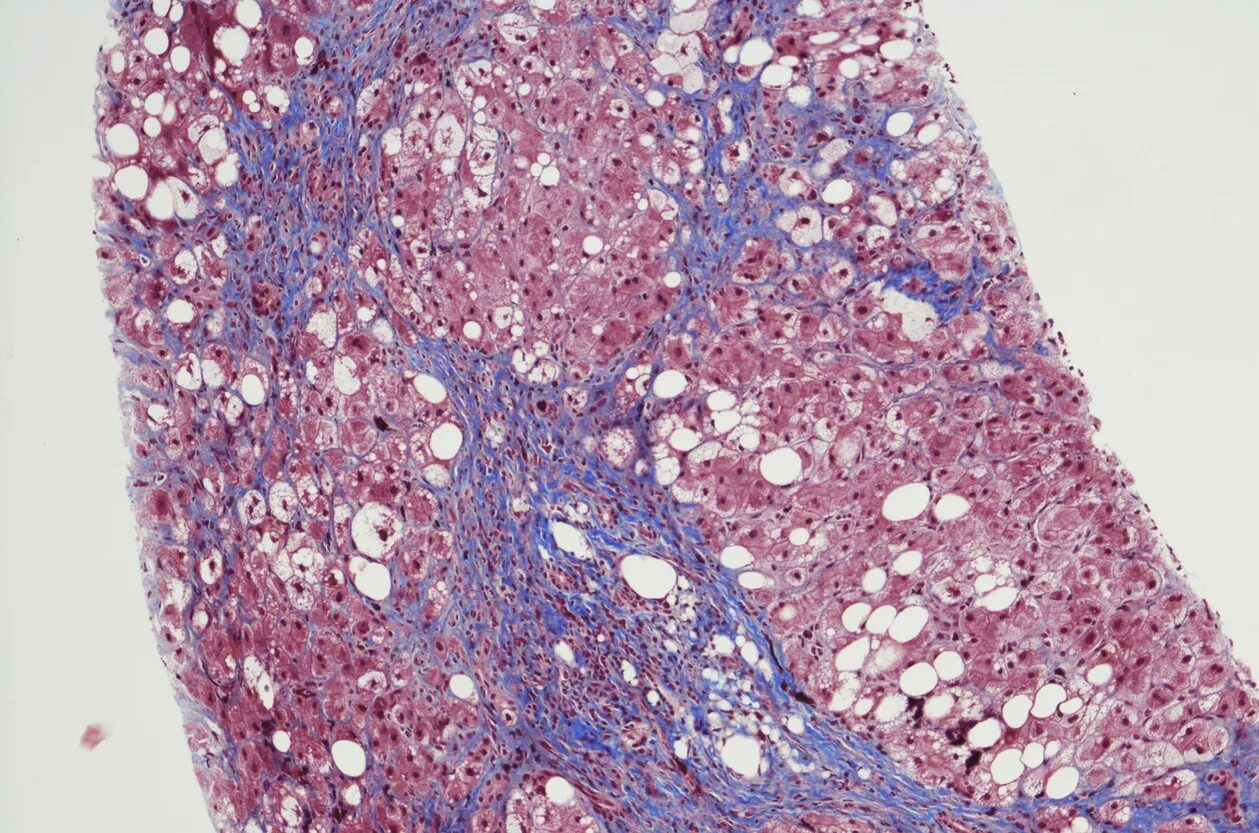

Диффузный стеатоз что это